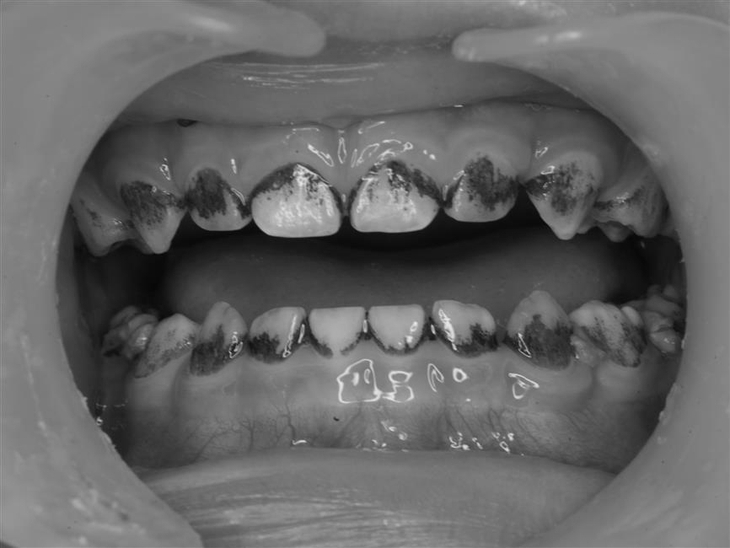

Răng bị kém khoáng sẽ đổi màu so với răng bình thường – Ảnh: BSCC

Đặc điểm được biết đến nhiều nhất là các tổn thương đốm trắng có ranh giới rõ do sự kém khoáng hóa của men răng gây ra. Trong những trường hợp nặng hơn, có hiện tượng vỡ men răng sau khi mọc, các tổn thương sâu răng không điển hình và đau, bao gồm cả nhạy cảm ngà.

Tổn thương có màu sắc rất phong phú, gọi là đốm trắng nhưng có thể có màu trắng, nâu, vàng… với các độ bão hòa màu sắc rất khác nhau.